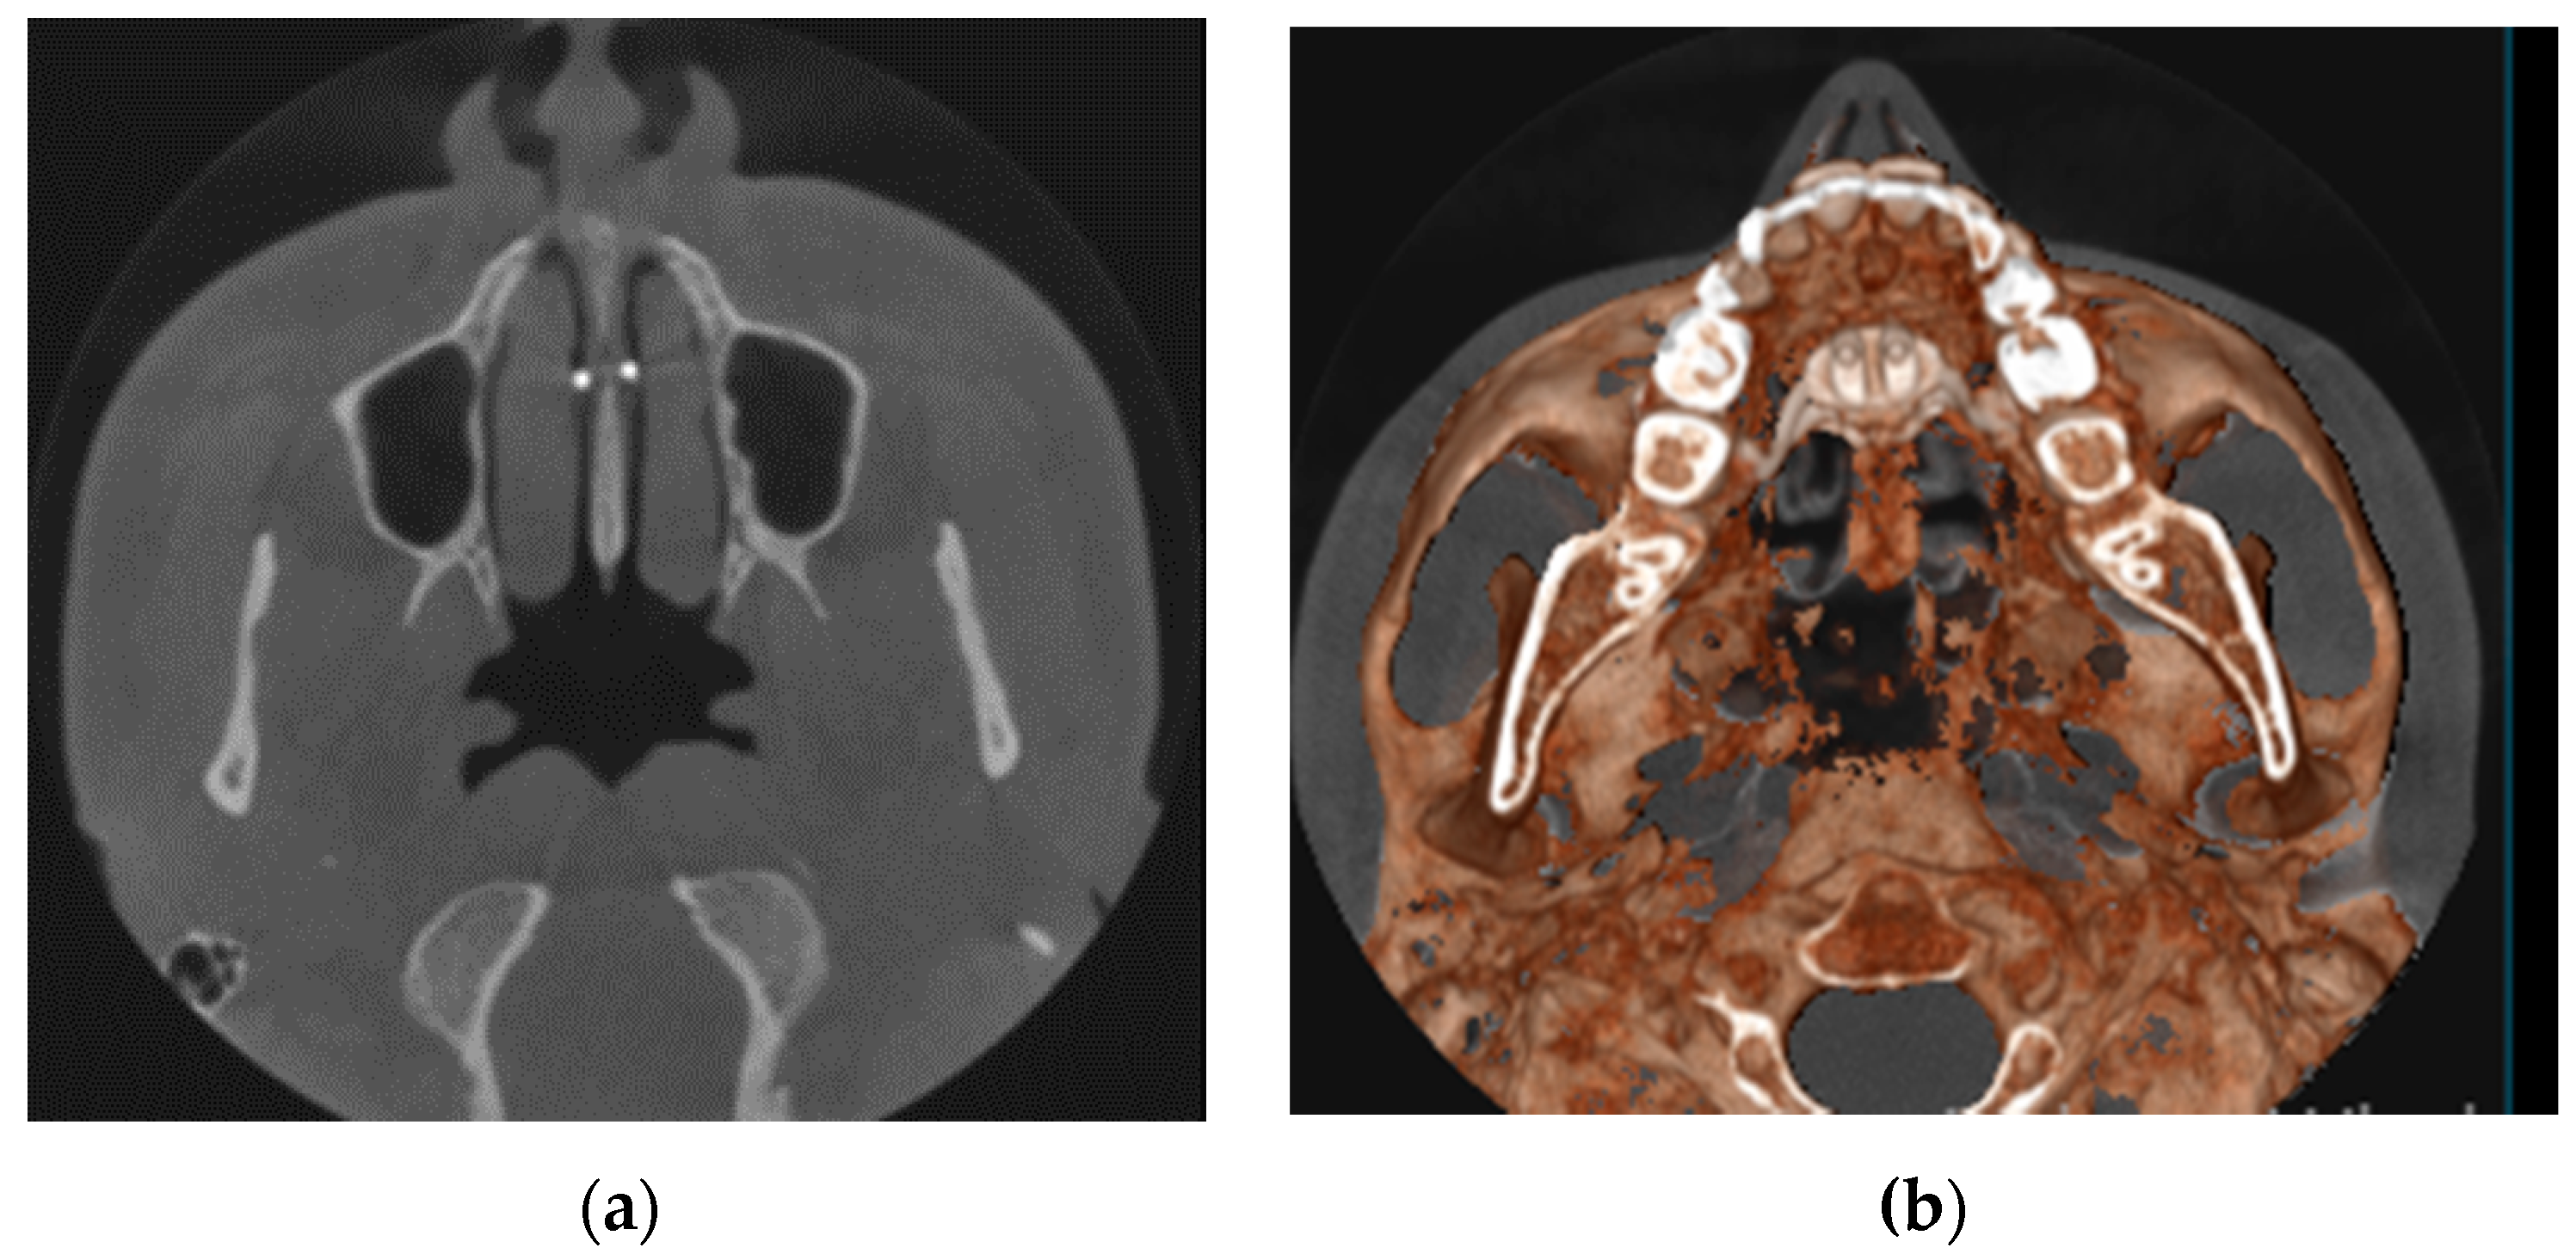

- MARPE associated with cortico-puncture therapy efficiently split the midpalatal suture in adults. The mean split at the anterior nasal spine (ANS) and posterior nasal spine (PNS) was 3.76 and 3.12 mm, respectively. The magnitude of the split at the PNS was smaller than at the ANS (by approximately 85% of the distance), showing that the opening of the midpalatal suture was almost parallel in the anteroposterior direction.

- Our results suggest that non-surgical palatal expansion, assisted by micro-implants and cortico-puncture, is achievable and predictable in young adults. This occurs in safe conditions without the need for more complex surgical treatment.

- The combination of MARPE and the cortico-puncture method proved to be a non-surgical treatment option to correct maxillary transverse deficiency in young adult patients. Cortico-puncture was able to weaken the suture interdigitation, thus facilitating the split.